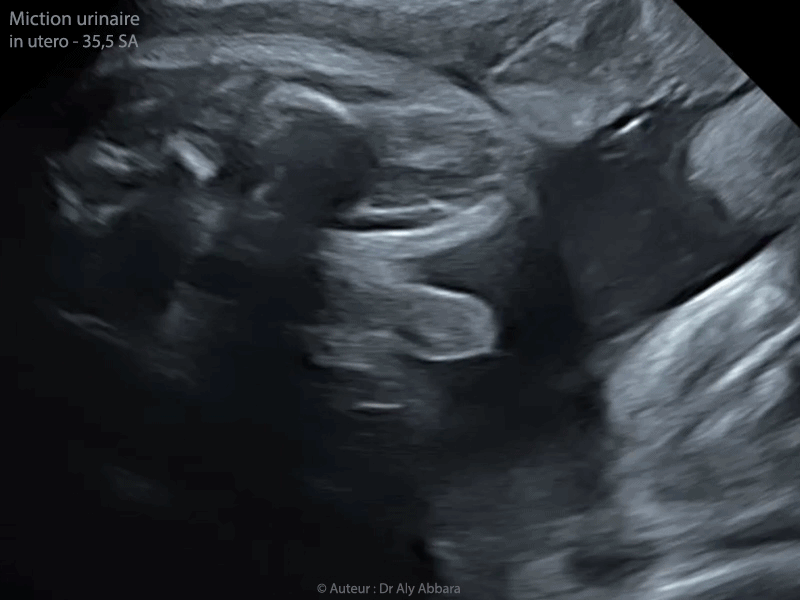

Miction urinaire chez un foetus de 35,5 SA

• Image échographique animée (fichier mp4) montrant une miction urinaire chez un fœtus de sexe masculin âgé de 35,5 SA.